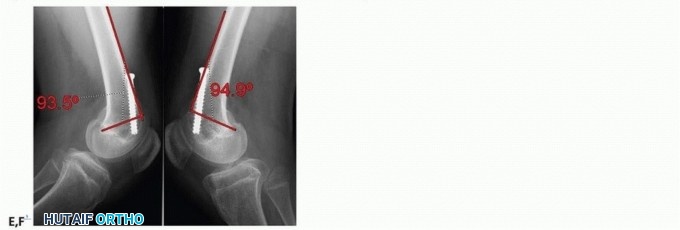

- FIG 8 • A,B. A 12-year-old boy with spastic diplegia who ambulates with a crouch gait, hamstring contracture, and knee flexion contracture. C,D. Intraoperative fluoroscopy demonstrating preoperative PDFA. The child underwent hamstring transfer and distal femoral guided growth with placement of 6.5-mm cannulated screw positioned anterior in the center of the distal femur. E,F. Postoperative lateral radiographs show improved PDFA and full extension on clinical examination. (Courtesy of UW Pediatric Orthopaedics.)